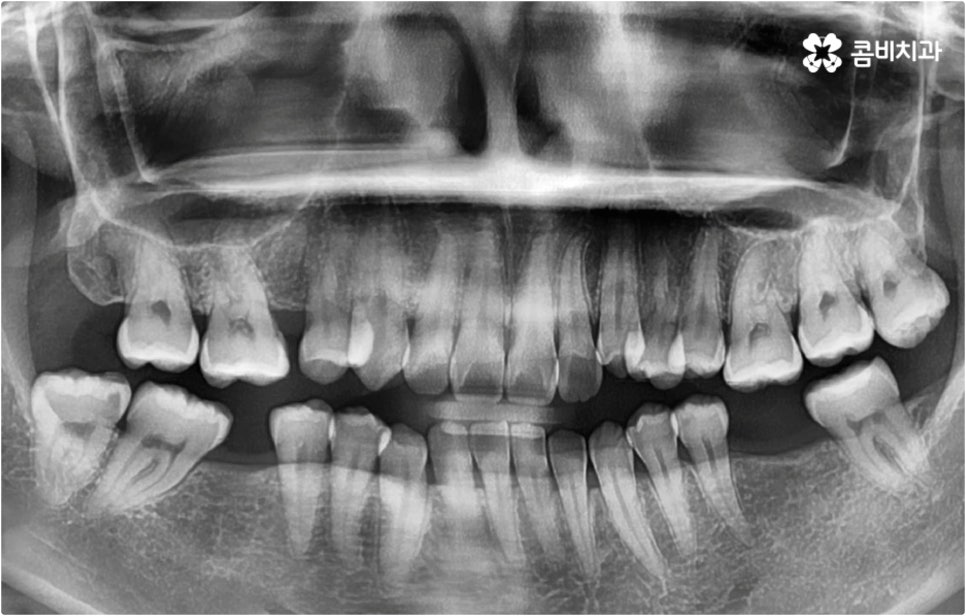

이때 현재 상황을 정밀하게 보여주는 3D CT, 미래 결과를 예측해서 보여주는 모르페우스와 같은 디지털 장비를 통해 전체 플랜을 자세하게 설명해 주고 중간 과정 역시 꼼꼼하게 브리핑해 주는 의료진과 함께 교정 치료를 진행한다면 조금은 길고 힘들게 느껴질 수 있는 전체 교정 과정에 보다 적극적이고 긍정적인 마음으로 임할 수 있을 거예요. 또한 앞서 말씀드린 것처럼 불편함을 줄여줄 수 있는 다양한 교정 장치와 방법 등이 있으니 가능한 선택지 내에서 자신의 상황에 최적화된 장치를 이용해 보시면 여러모로 도움을 받으실 수 있습니다.

이와 같이 치아설측교정 과 콤비교정은 브라켓을 치아 안쪽으로 붙여서 치료하는 방식이기 때문에 굉장히 고난도의 복잡한 교정 치료라고 할 수 있습니다. 교정에 대한 높은 이해도와 해부학적으로 뛰어난 노하우, 풍부한 경험을 통해 축적한 세심한 기술력을 갖추고 있는 의료진에게 치료를 맡기는 것이 중요하며 정밀 디지털 검진 장비를 통한 정확한 검사 결과를 바탕으로 무리하지 않게 진행하실 필요가 있어요. 또한 양치질을 할 때 음식물 제거가 쉽지 않으므로 환자분들 본인이 평상시 신경써서 닦아주시는 것은 물론 꼼꼼한 케어시스템을 통해 주기적으로 관리해 주는 치과에서 교정 치료 및 사후 유지 관리까지 철저하게 받아보시길 권유드리고 있습니다.